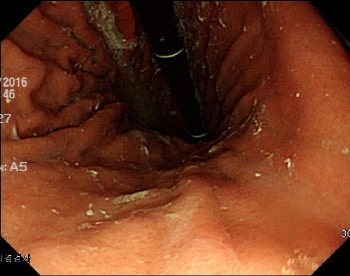

그래서 오늘은 내시경 전의 주의사항이나 특정 약 복용은 괜찮은지 등에 대해 이야기하고자 합니다.내시경 검사란?내시경으로 신체의 다양한 내강을 관찰, 검사함으로써 검사가 필요한 장기에 내시경을 삽입하고 기체나 액체로 내강을 부풀리면서 장기의 구조와 상태를 파악하는 검사 방법입니다.

수술로 몸을 절개하지 않아도 눈으로 조직의 병변을 확인할 수 있다는 장점이 있습니다.

내시경 검사로 단순한 염증성 질환부터 친정, 암, 용종 등 다양한 질환을 판단할 수 있습니다.